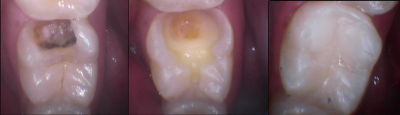

Gallery

Galeria